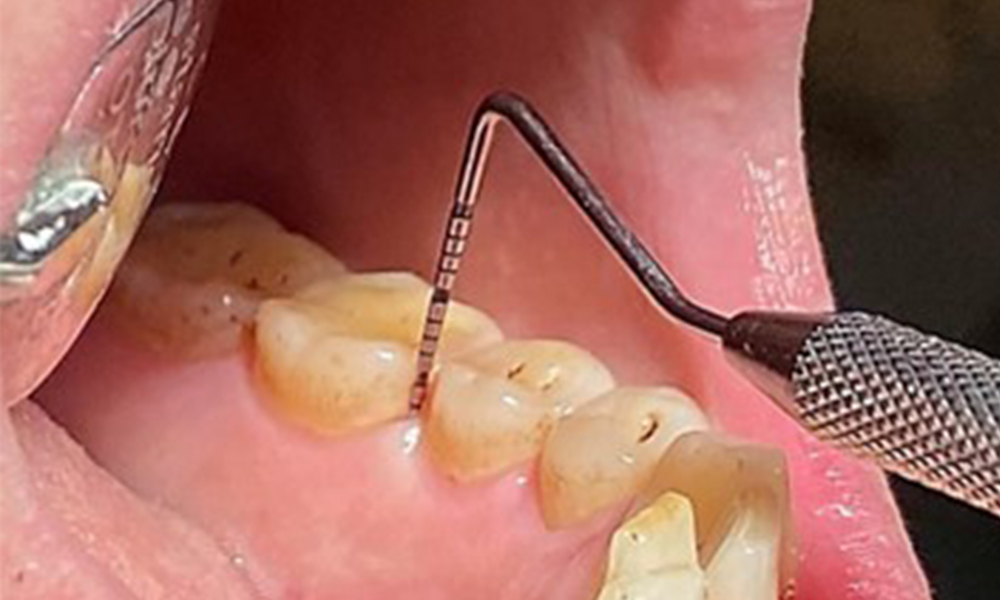

Due to the otherwise favourable general medical condition, the needs determined during the intraoral examination will be decisive for their treatment. It will be essential to periodically determine the probing depths. Gingival bleeding decreases in smokers, which is why the clinical diagnosis of periodontitis can only be made by probing (Fig. 7). Placing exclusive focus on the determination of bleeding indices may obscure existing periodontitis or gingivitis. (5)

Pocket probing (BOP) with depiction of tooth 36 lingual

Fig. 7 Pocket probing (BOP) with depiction of tooth 36 lingual, © Dr R. Krapf